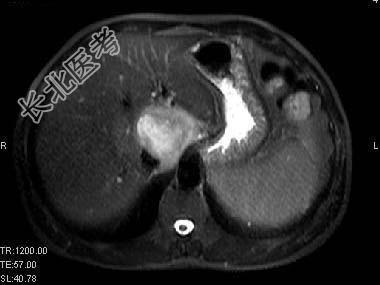

单项选择题根据所提供的图像,最可能的诊断是 ( )

A、肝囊肿

B、胆管细胞癌

C、先天性胆管扩张

D、肝脓肿

E、以上都不是